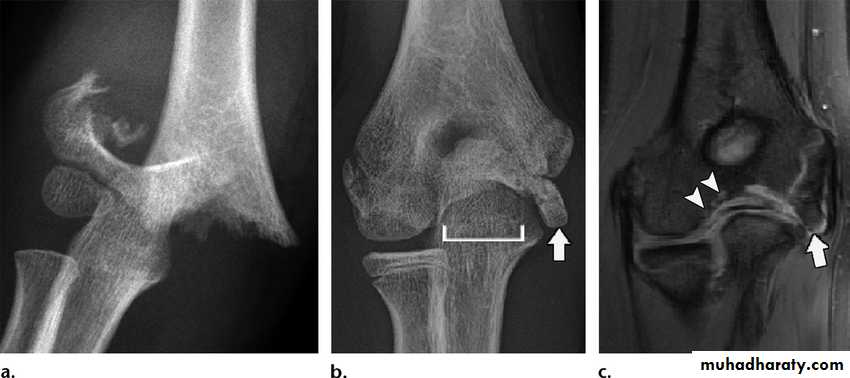

Lateral Condyle Fractures

Common fracture, representing approximately 15 percent of elbow trauma in children.Usually occurs from a fall on an outstretched hand in varus.

The diagnosis of a lateral condyle fracture can be challenging. Fracture lines are sometimes rarely visible.Since most of the structures involved are cartilageneous, it is very difficult to know the exact extent of the fracture.

X-ray;

In lateral condyle fractures the actual fracture line can be very subtle since the metaphyseal flake of bone may be minor.

The fracture fragment is often rotated.

Lateral condyle fracture: displacement

Displacement < 2mm .> 2mm gap, but fragment close to humerus.

Wide displacement and rotation.

Treatment strategies are based on the amount of displacement.